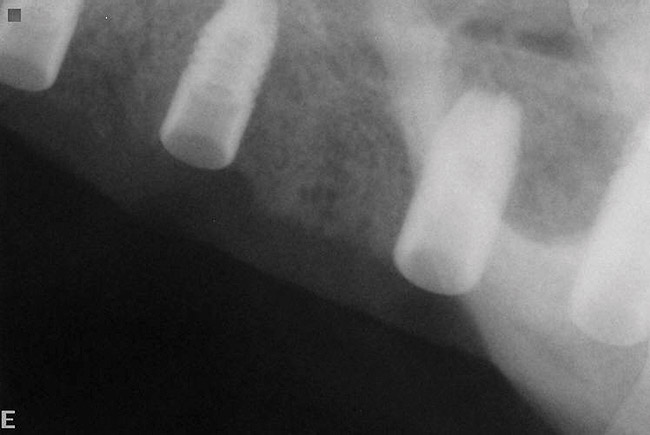

Figure 20  Post-placement periapical radiographs.

Figure 20

Figure 21  Post-placement periapical radiographs.

Figure 21